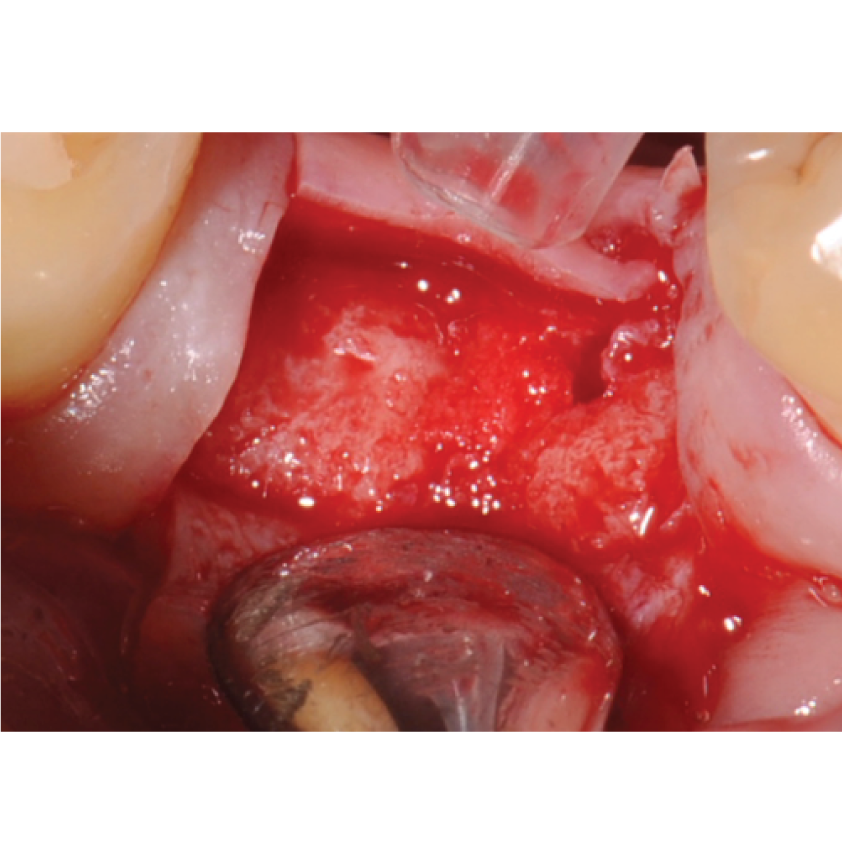

Director’s Clinical Cases

Director’s Clinical Cases